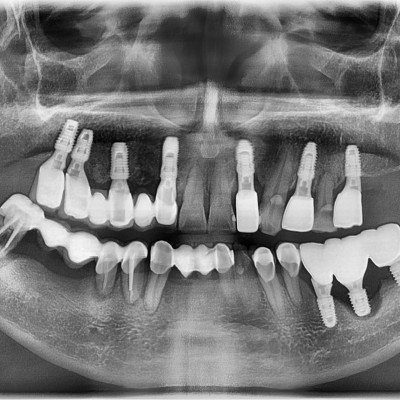

• 7

임플란트 재수술 타원임플란트 #14 파절되어 재수술

작성자 이턱이 작성일 01-27 조회 105